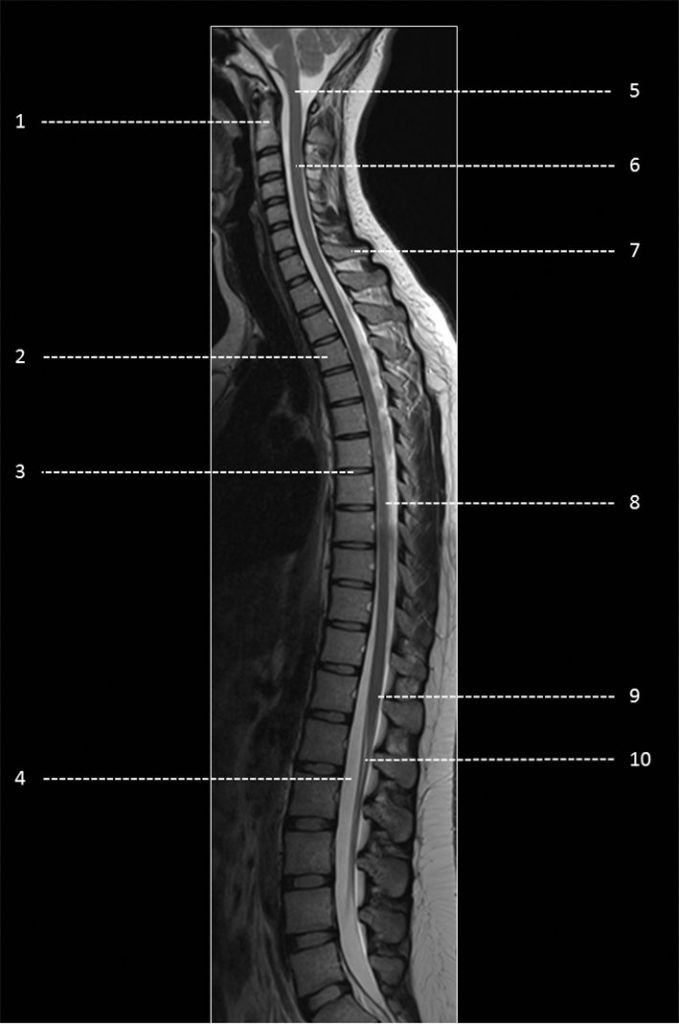

Fig. 48.11 Coupe sagittale (IRM) en pondération T2 du rachis cervico-thoraco-lombaire.

1. Deuxième vertèbre cervicale (C2). 2. Corps vertébral de T3. 3. Disque intervertébral T6-T7. 4. Liquide cérébrospinal. 5. Jonction cervico-médullaire. 6. Moelle spinale cervicale. 7. Processus épineux de C7. 8. Moelle spinale thoracique. 9. Cône terminal. 10. Racines de la queue de cheval.

Source : CERF, CNEBMN, 2022.